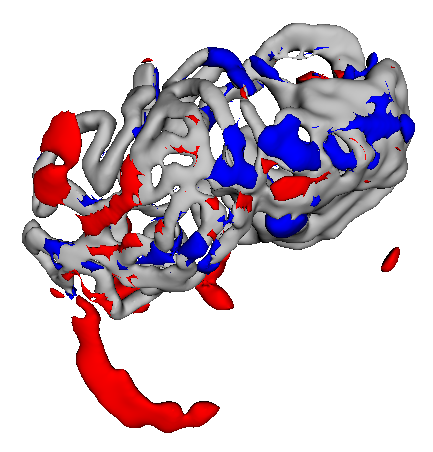

Figure 3 shows example segmentation results in 3D. The result corresponding to ‘feat. & out. level DA’ in Table 1 is compared to ours. We note that the only difference between them is whether the feature disentanglement is involved for the domain adaptation, thus could show its effectiveness. Fewer errors are observed for the proposed method. We believe this is because the proposed method explicitly concentrates on the features more transferable across the datasets, the non-intensity features in this work, by disentangling those features and applying adversarial learning directly to them during the adaptation process. Example reconstruction results from the auto-encoding architecture as well as segmentation results in coronal view can be found in supplementary material.

A

B

B

C

C